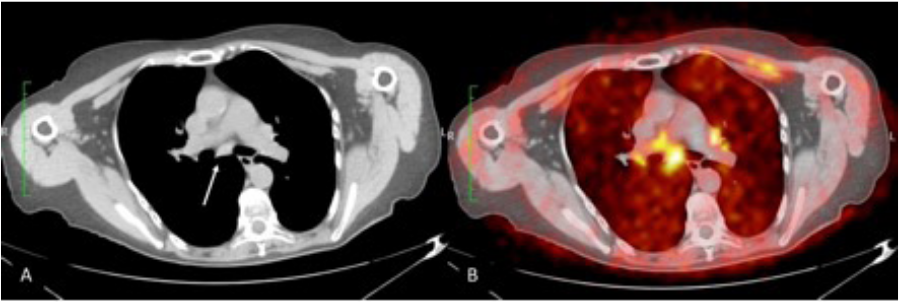

Figura 2. Paciente femenina con diagnóstico de melanoma en pie derecho hace 6 años. A. Ganglio de 9mm de diámetro corto en nivel VII subcarinal (flecha blanca). B. Captación del mismo ganglio con SUV de 4,5, compatible con malignidad. Fuente. Base de datos de la investigación. Unidad PET-CT HECAM. Elaborado por. Autores.